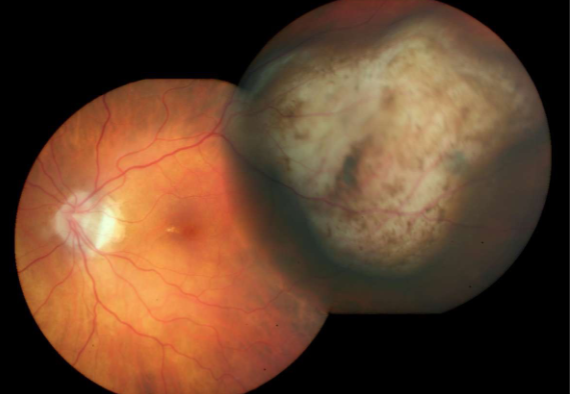

choroidal melanoma

melanoma

melanoma

melanoma

melanoma

melanoma

melanoma

melanoma

melanoma

melanoma

melanoma

melanoma

melanoma

melanoma

melanoma

melanoma

melanoma